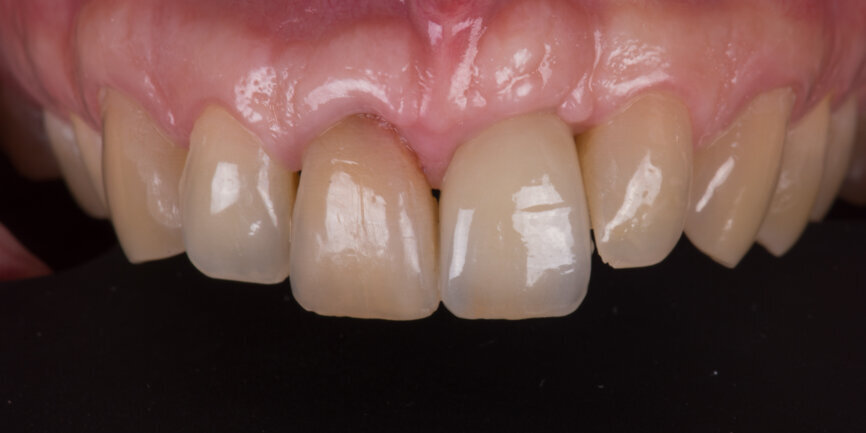

Two months after the extraction of tooth #12, an implant level impression was taken for final restoration using a digital scan body (Fig. 18) and a digital intra-oral scanner (TRIOS, 3Shape). A zirconia cantilevered fixed implant-supported bridge was fabricated according to a fully digital workflow (Figs. 19 & 20). The screw-retained bridge was then torqued to 35 N cm (Figs. 21 & 22). The follow-up, ten months after implant placement, showed a well-preserved gingival contour (Figs. 23 & 24).

Immediate implant placement and temporisation when properly indicated have three main advantages: timing, biology and prosthetics. The treatment time and number of surgical procedures are reduced compared with a delayed approach. From a biological standpoint, using a slow-resorbing material to fill the gap between the implant and the buccal plate allows predictable preservation of the bone volume. The provisional crown supports the gingival architecture and helps maintain the pre-existing positions of the gingival margin and of the mesial and distal papillae.

When replacing multiple adjacent teeth, a staged approach when possible for the extractions will give better results and the use of a cantilever can allow better soft-tissue preservation. Placing an implant-supported provisional crown on the day of surgery simplifies temporisation in the anterior area, allowing the patient to leave the office on the same day with a fixed provisional.